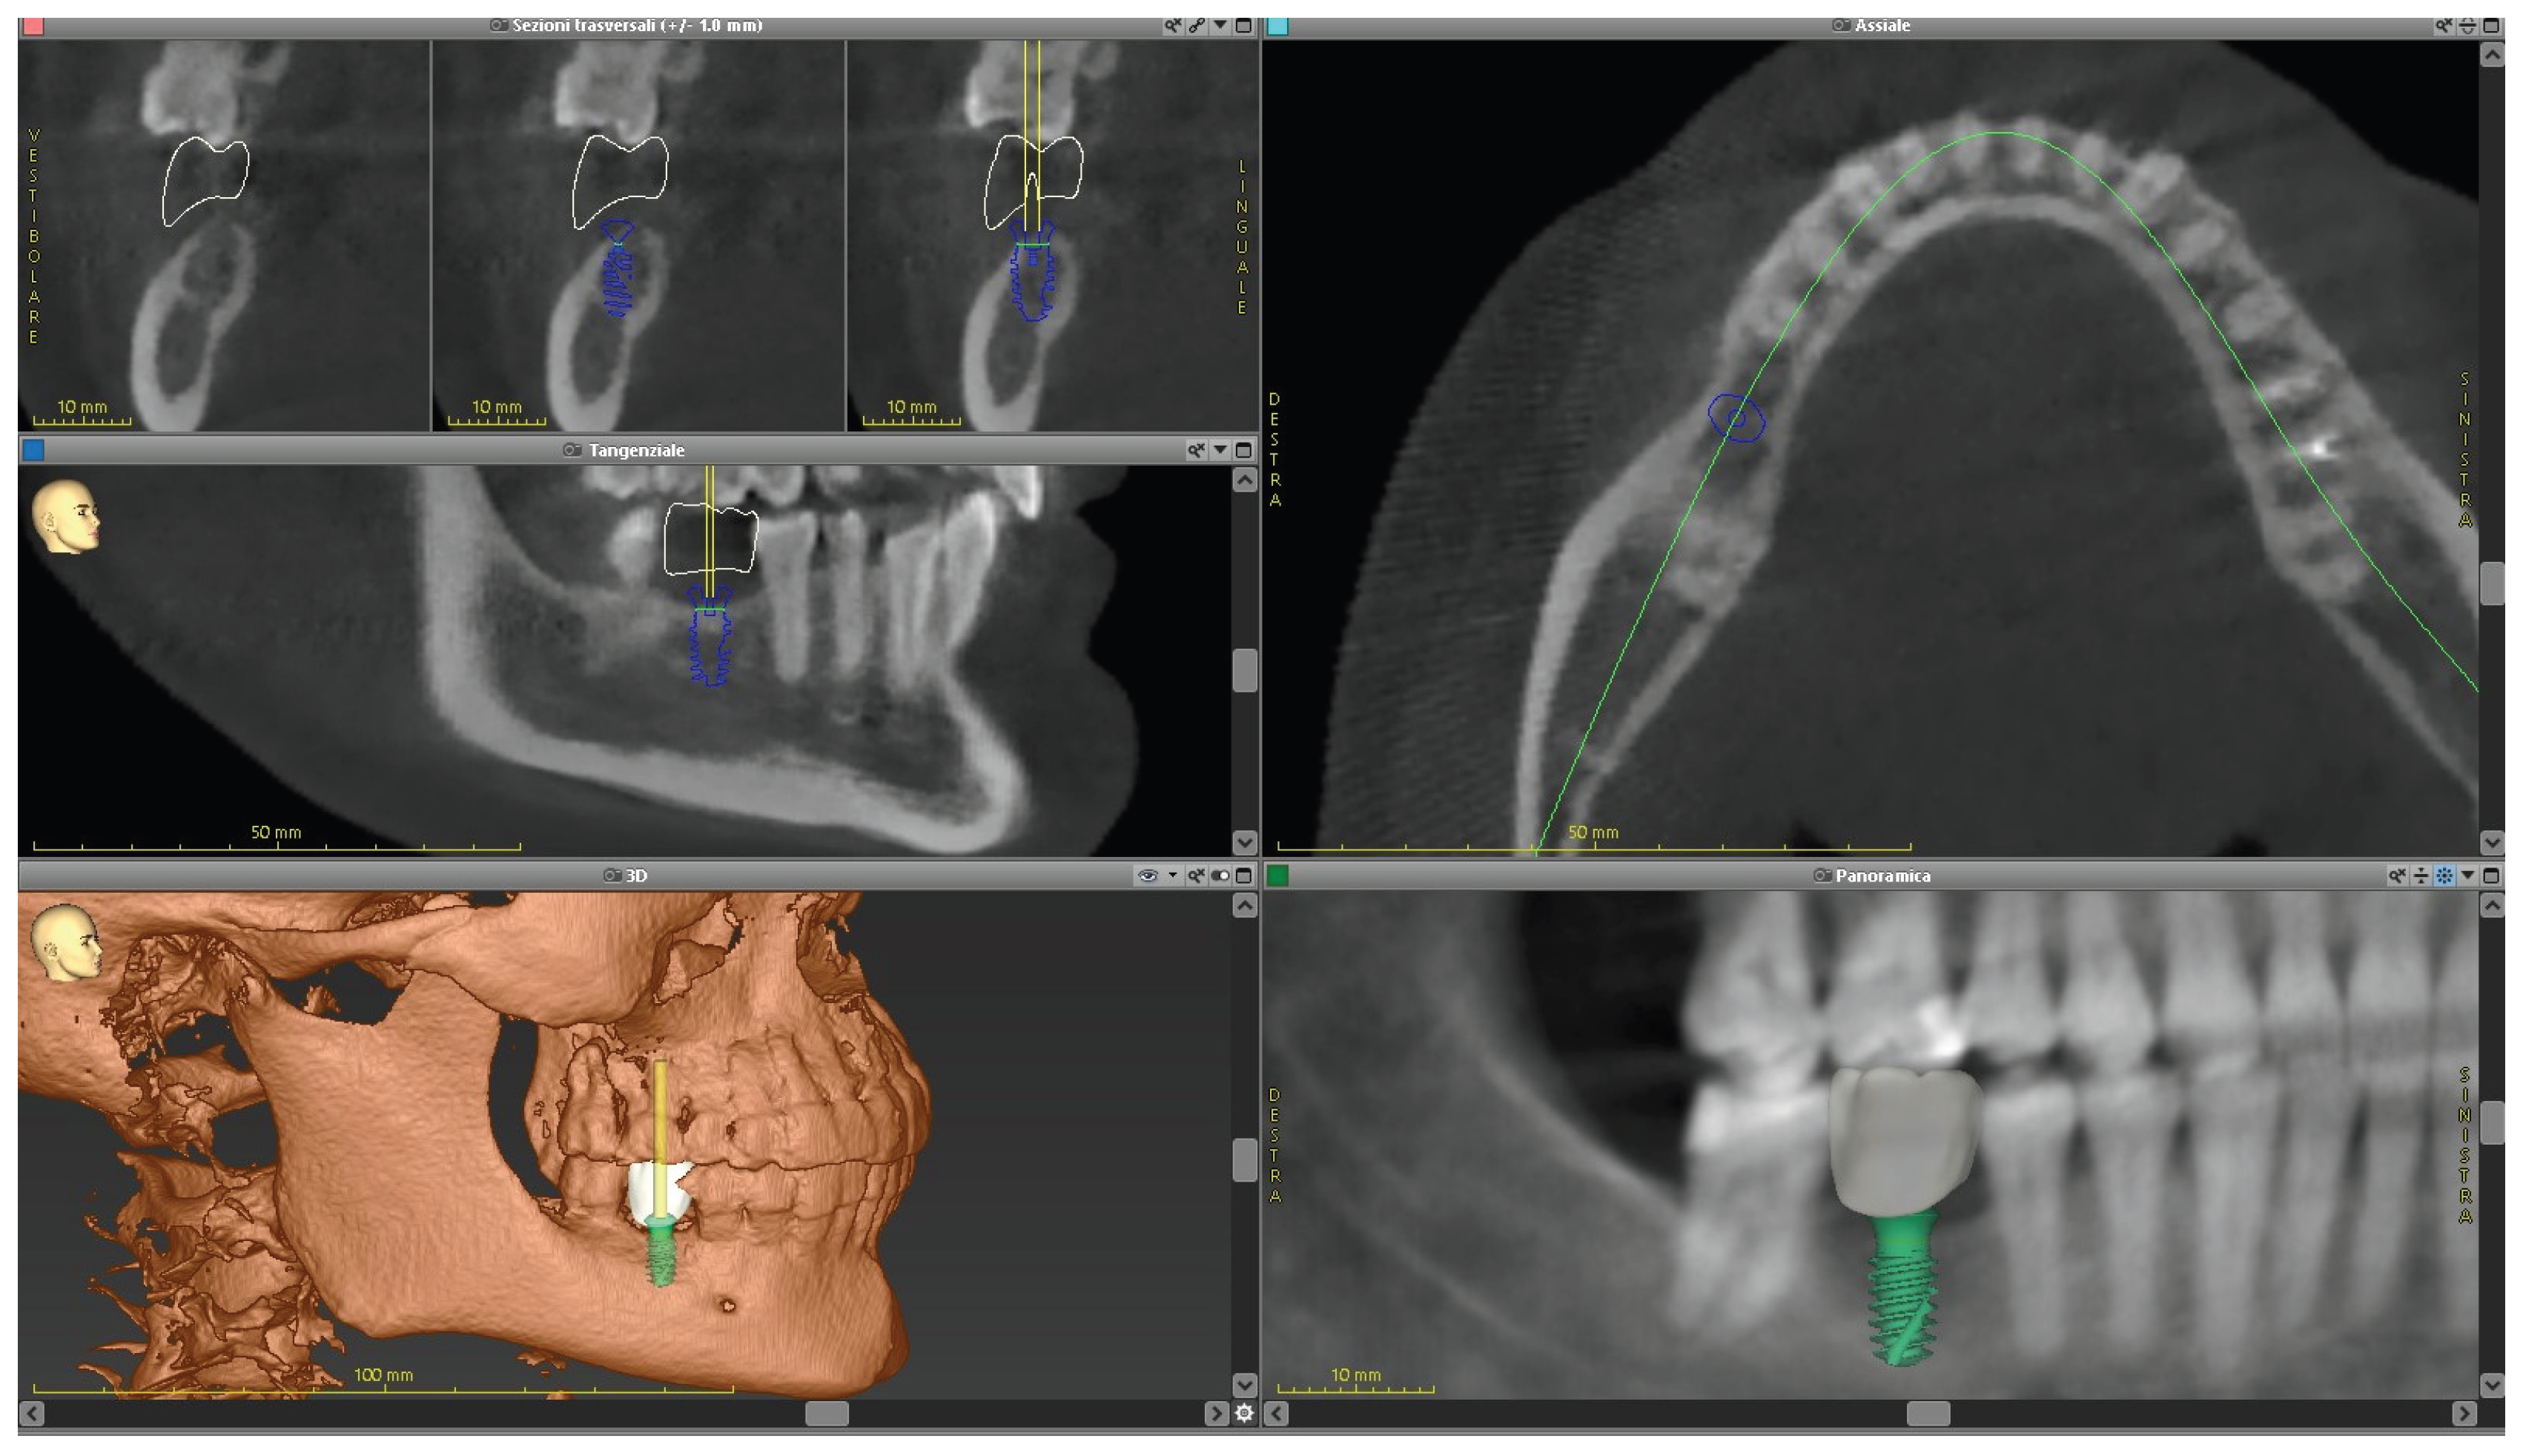

2.2. Cone Beam CT Analysis

| CBCT (t0) | |

| after 8 months | Retainers + CBCT (t1) + final photos |